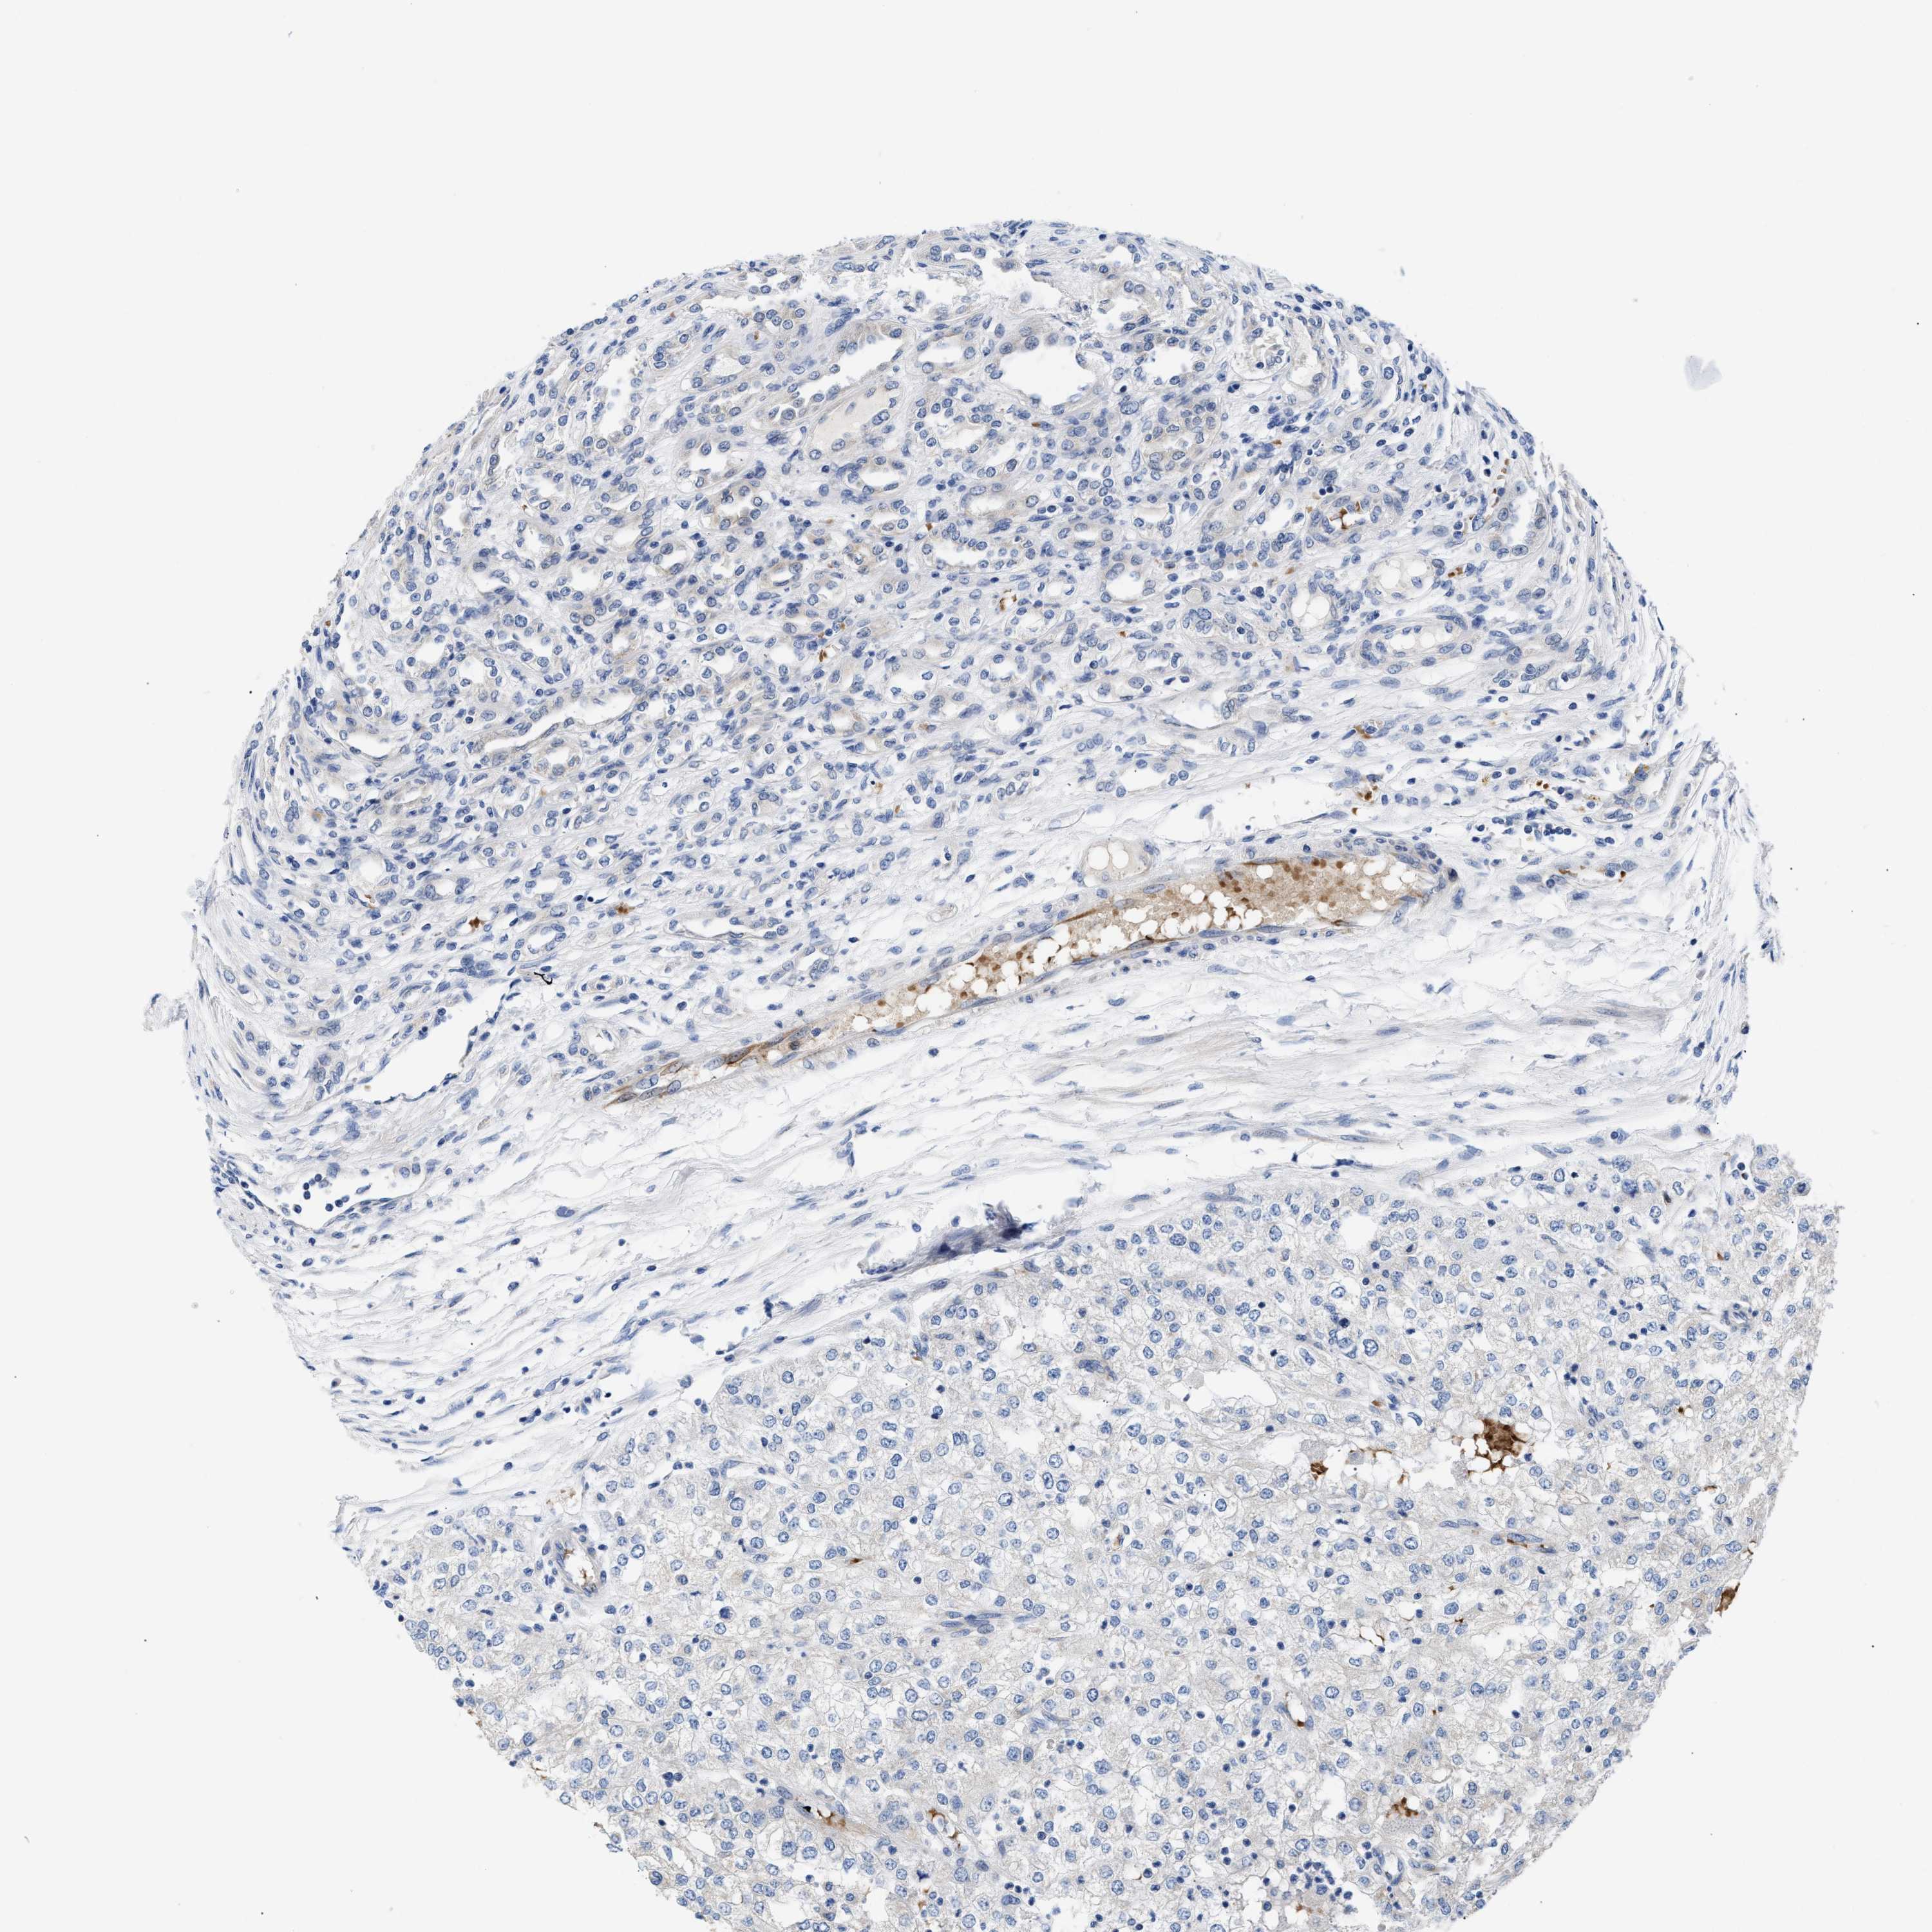

KIDNEY RENAL CLEAR CELL CARCINOMA (VALIDATION) - Interactive survival scatter ploti

The Survival Scatter plot shows the clinical status (i.e. dead or alive) for all individuals in the patient cohort, based on the same data that underlies the corresponding Kaplan-Meier plots. Patients that are alive at last time for follow-up are shown in blue and patients who have died during the study are shown in red.

The x-axis shows the expression levels (FPKM) of the investigated gene in the tumor tissue at the time of diagnosis. The y-axis shows the follow-up time after diagnosis (years). Both axes are complimented with kernel density curves demonstrating the data density over the axes. The top density plot shows the expression levels (FPKM) distribution among dead (red) and alive patients (blue). The right density plot shows the data density of the survived years of dead patients with high and low expression levels respectively, stratified using the cutoff indicated by the vertical dashed line through the Survival Scatter plot. This cutoff is automatically defined based on the FPKM cutoff that minimizes the p-score. The cutoff can be changed by dragging the vertical line or by entering a cutoff value in the square labeled "Current cut-off".

Under the Survival Scatter plot the p-score landscape (black curve; left axis) is shown together with dead median separation (red curve; right axis). Dead median separation is the difference in median mRNA expression between patients who have died with high and low expression, respectively. It is calculated as follows: median FPKM expression of dead patients with high expression - median FPKM expression of dead patients with low expression. This is intended to aid the user in visually exploring custom cutoffs and the associated p-scores and dead median separation.

Individual patient data is displayed and can be filtered by clicking on one or more of the category buttons on the top of the page. Categories describing expression level and patient information include: high, low, alive, dead, female, male and tumor stages. The scale of the x-axis can be toggled between linear and log-scale by clicking on the "x log" button. Mouse-over function shows TCGA ID, patient information and mRNA expression (FPKM) for each patient.

& Survival analysisi

Kaplan-Meier plots summarize results from analysis of correlation between mRNA expression level and patient survival. Patients were divided based on level of expression into one of the two groups "low" (under cut off) or "high" (over cut off). X-axis shows time for survival (years) and y-axis shows the probability of survival, where 1.0 corresponds to 100 percent.

RINT1 is not prognostic in Kidney Renal Clear Cell Carcinoma (validation)

Best expression cut offi

Based on the FPKM value of each gene, patients were classified into two groups and association between prognosis (survival) and gene expression (FPKM) was examined. The best expression cut-off refers the FPKM value that yields maximal difference with regard to survival between the two groups at the lowest log-rank P-value. Best expression cut-off was selected based on survival analysis .

When clicking on this number, the vertical dashed line indicating cut-off, the interactive survival plot, and the Kaplan-Meier curve will be adjusted to show results based on the best expression cut-off.

: 14.26

P scorei

Log-rank P value for Kaplan-Meier plot showing results from analysis of correlation between mRNA expression level and patient survival.

N/A

TCGA RNA samplesi

RNA-seq data is reported as average FPKM (number Fragments Per Kilobase of exon per Million reads), generated by the The Cancer Genome Atlas (TCGA) .

Normal distribution across the dataset is visualized with box plots, shown as median and 25th and 75th percentiles. Points are displayed as outliers if they are above or below 1.5 times the interquartile range. FPKM values of the individual samples are presented next to the box plot.

Average pTPM 15.4

Number of samples 100